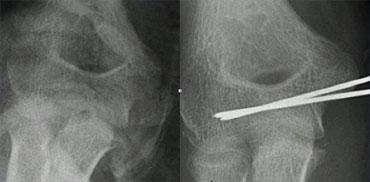

Supracondylar fractures. In A the anterior humeral line passes through the anterior third of the capitellum and in B even more anteriorly. Notice positive posterior fat pad sign in both cases

Gãy xương trên lồi cầu (2)

Nếu chỉ có di lệch tối thiểu hoặc không có di lệch, các gãy xương này có thể ẩn trên phim X-quang.

Dấu hiệu duy nhất sẽ là dấu hiệu đệm mỡ dương tính.

Thường có một số di lệch và đường cánh tay trước sẽ không đi qua trung tâm của chỏm con mà đi qua một phần ba trước hoặc thậm chí phía trước chỏm con (hình).